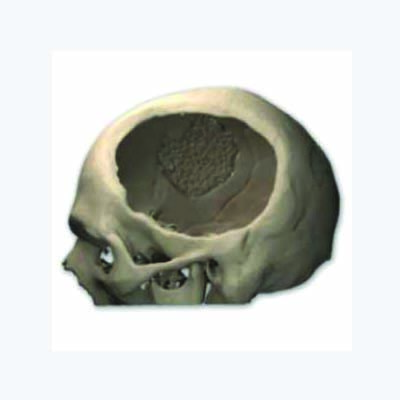

Medicad Implants is a state of the art technology firm specialized in providing customized solutions for hard tissue replacement and cranial implant in India. We are a synergy of motivated and experienced Engineers, Medical Practitioners and Designers striving to help surgeons for cranial implant india for their patients.

Skull injury as a result of tumor, decompressive trauma, infections or fractures from road accidents can be a life altering event. In addition to the physical changes that such an injury may bring, it could also lead to Psychological stress affecting the persons day to day activities.

Patient specific” Technology is one of the latest development in the medical field aimed at providing more accurate and lasting healthcare to patients. It synergically ties the medical imaging techniques with reverse engineering and rapid manufacturing concepts long being used in Aerospace and automobile fields to provide a unique solution on a case by case basis.